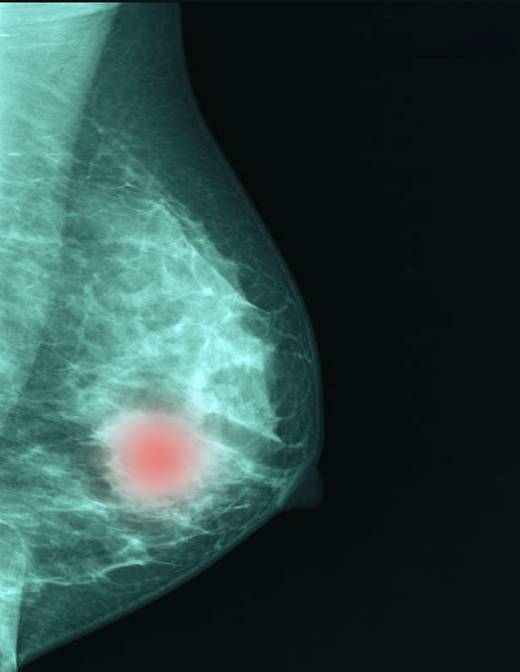

운동이 유방암의 가장 좋은 예방법이다. 지속해서 운동하면 에스트로겐이 적게 생성되고 복부에 지방이 덜 쌓일 뿐만 아니라 인슐린 수치도 낮춘다. 하루 30분씩 일주일에 3~4일 걷기, 자전거 타기, 수영, 에어로빅, 등산 등 유산소 운동이 도움 된다.

에스트로겐의 효과를 떨어뜨리는 식습관도 중요하다. 동물성 지방이나 오메가-6 지방 대신 오메가-3 지방을 섭취하는 게 좋다. 황록색 채소, 과일, 콩, 곡물 등 섬유질이 많은 식품 섭취를 늘린다. 당을 과도하게 섭취하지 않는 것도 중요하다. 당 흡수가 늘수록 당을 산화시키기 위해 인슐린이 더 많이 분비돼서다. 인슐린이 많이 분비되면 에스트로겐 수용체와 상호작용이 활발해져 유방암 발병 위험을 높일 수 있다.